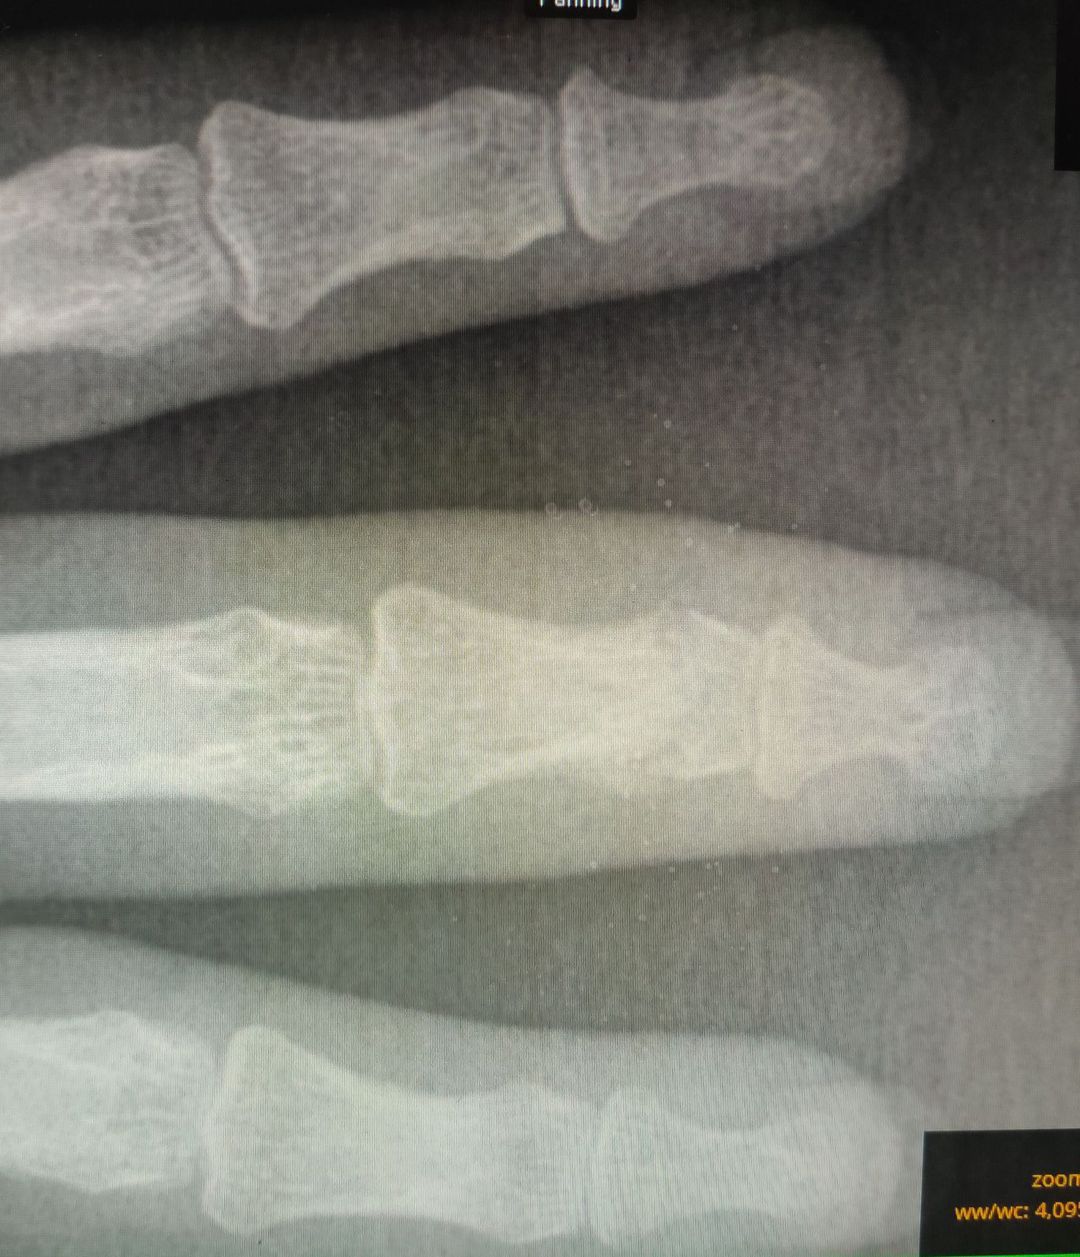

Diagnosis?

No,thats regeneration of the fracture